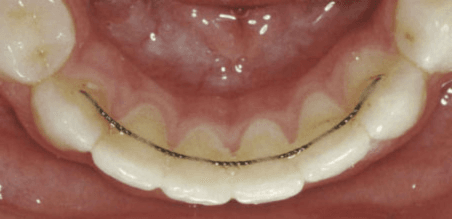

Pour maintenir le résultat, une contention permanente est nécessaire. Selon votre situation, nous posons soit un fil métallique collé à l'intérieur des incisives, soit une gouttière de contention sur mesure. Dans les deux cas, la contention est définitive : elle fait partie intégrante du traitement.

Appareil de contention orthodontique pour maintenir les dents après traitement